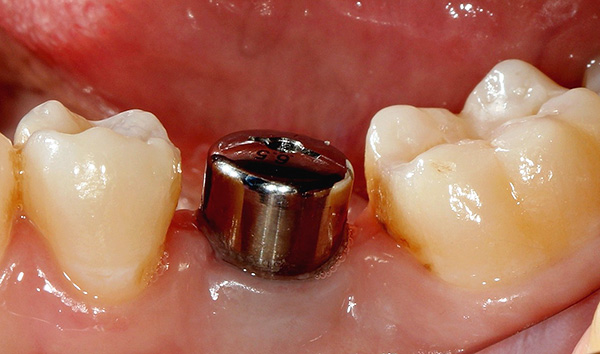

Четвърти етап: Протетичен етап – поставяне на зъбите. Взема се дигитален отпечатък и се изпраща за изработка на зъбите в зъботехническа лаборатория. Според желанието на пациента зъбите може да се изработят от металокерамика или цирконий